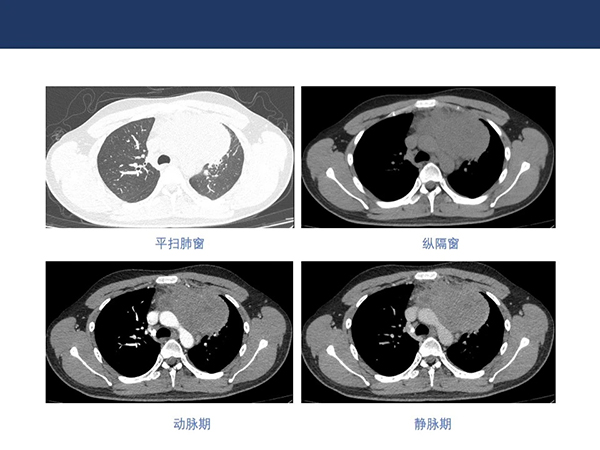

【院庆51周年】放射科:纵隔淋巴瘤